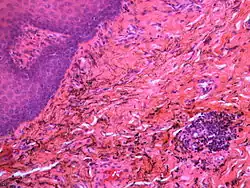

Granular deposits of silver sulfide along elastic fibers of the connective tissue of the oral mucosa. Low chronic inflammatory changes in the form of a lymphocytic aggregate (bottom right)

Silver sulfide deposits are found in proximity to small vessels in the oral mucosa

If necessary, the diagnosis can be confirmed histologically by excisional biopsy, which excludes nevi and melanomas.[3]: 138  If a biopsy is taken, the histopathologic appearance is:[1]

• Pigmented fragments of metal within connective tissue

• Staining of reticulin fibers with silver salts

• A scattered arrangement of large, dark, solid fragments or a fine, black or dark brown granules

• Large particles may be surrounded by chronically inflamed fibrous tissue

• Smaller particles surrounded by more significant inflammation, which may be granulomatous or a mixture of lymphocytes and plasma cells